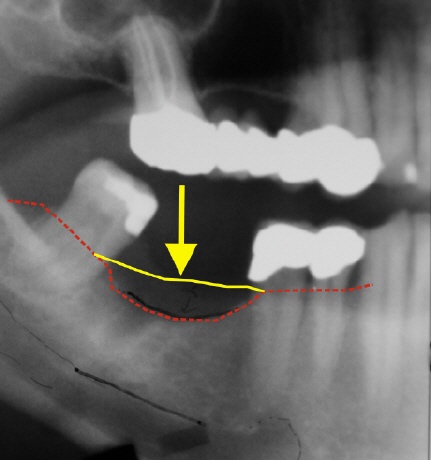

Das Bild oben zeigt eine Zahnlücke im Unterkiefer (gelber Pfeil). Das langjährige fehlen des Zahnes blieb in diesem Fall nicht ohne Folgen. Der Knochen ist in seiner Höhe stark abgebaut. Zum Vergleich, die gelbe Linie entspricht dem ehemaligen Knochenverlauf, die rote gestrichelte Linie zeigt den momentanen Knochenverlauf. Das was zwischen den Lienien ist, ist die verlorene Knochenhöhe. In diesem Fall sind das etwa 7 mm bisher.